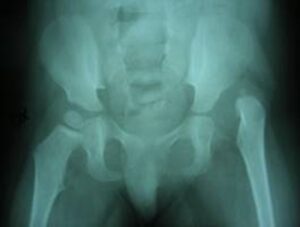

Deformità e lussazione delle anche

Vai alla scheda dedicata alla lussazione delle anche in spina bifida